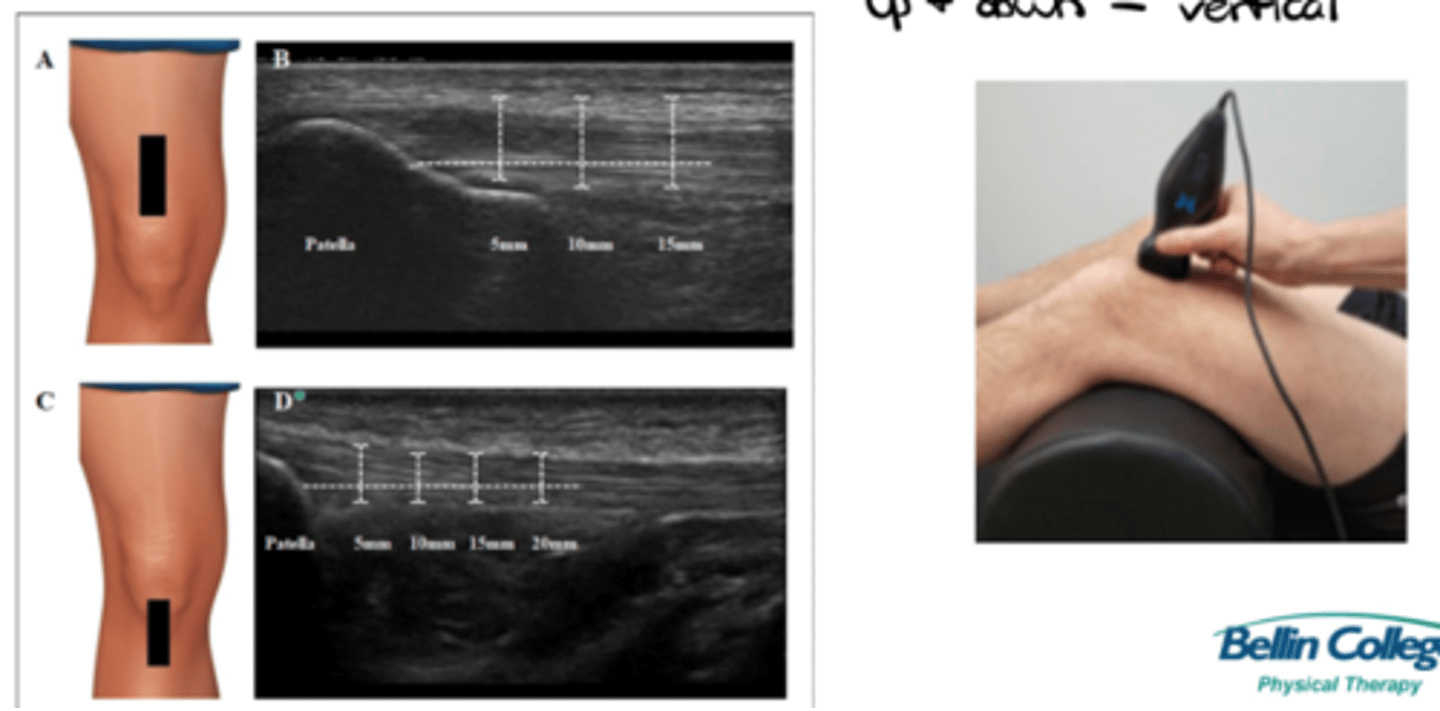

___________: probe orientation that allows for a longitudinal/vertical/up & down scan

Long axis

___________: probe orientation that allows for a transverse/horizontal/left & right scan

Short axis

What would a transverse vs. longitudinal ultrasound of the shoulder look like?

See image.